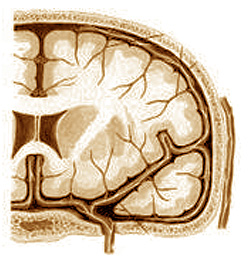

Dans certaines circonstances (énumérées ci-dessus), cette contracture provoque un déplacement anormal des vertèbres cervicales et des os de la tête, ce qui exerce une pression sur les vaisseaux sanguins cérébraux, ce qui ralentit le flux sanguin (photo 4). Il se crée un déficit en oxygène, qui est déjà en mesure de générer la migraine.

L’organisme se trouve contraint de prendre des mesures urgentes pour augmenter l’apport d’oxygène avant que des perturbations sérieuses se produisent dans le cerveau. Ceci est réalisé par un afflux de sang artériel, déclenché par des mécanismes réflexes. Mais, comme la sortie du sang du crâne est toujours bloquée à cause de la contraction, cela va entraîner de l’hypertension intracrânienne et donc, d’ici la sensation de douleur insupportable.

Les choses peuvent se calmer un laps de temps après la médication, mais comme la principale cause – la vieille contracture musculaire – persiste, la récidive de la crise est inévitable dès que l’un des facteurs déclencheurs survient.